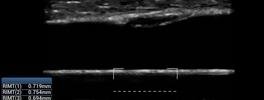

• RIMT (RF-Data based IMT) For Atheromatous Changes in Carotid Artery